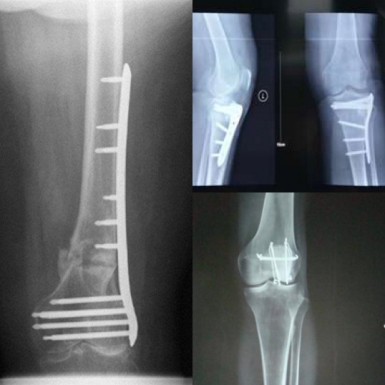

青年男性,一年前车祸致右下肢大范围创伤合并胫骨平台粉碎骨折,取钢钉术后半月,仍存在严重的膝关节僵直,主动活动范围15-40度,被动活动范围10-55度,髌骨粘连活动受限,膝关节周围压痛明显,膝关节屈伸不利,步态异常,进入我科后,诊断为关节粘连分级为最严重的4级,并存在肌肉神经控制下降,髌骨粘连,股四头肌萎缩,以及力量下降等多种问题。对患者采用深部肌肉刺激仪(DMS)放松并激活肌肉,ARTROMOT®ACTIVE-K增强本体感觉训练和关节活动训练,手法采用关节松动和软组织松解,诱发股四头肌收缩,以及强化的肌力和平衡训练。患者在整个康复过程中仅有轻微疼痛,完全可以忍受。经过一个月的正规康复治疗,主动关节活动达到5-85度,被动关节范围0-105度,步态基本正常,可以继续上班。

图为CPM及手法康复治疗                图为治疗前后膝关节活动度比较